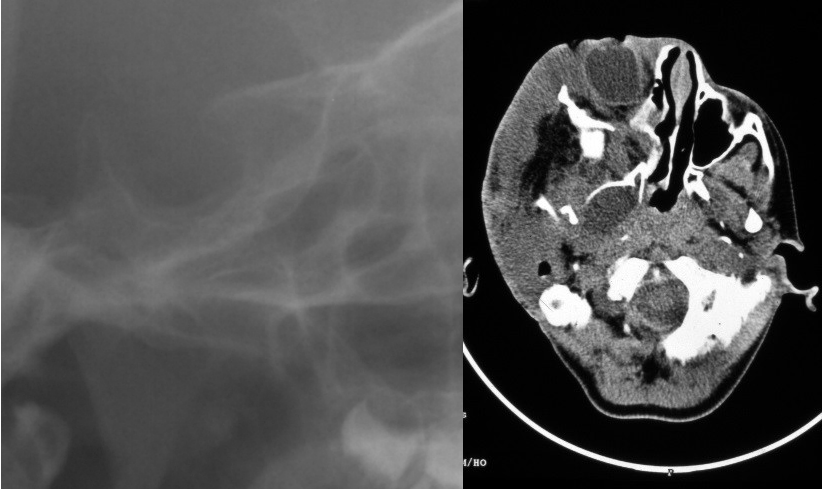

Figure 3: Radiographs of a NF1-affected individual with both OPG and PNF. Upper left side: Cropped image of lateral cephalogram of a NF1-affected 18 year-old female with bilateral OPG and j-shaped sella on lateral radiograph (anterior to the right). Upper right side: Computed tomography image illustrates sella turcica morphology: J-shaped sella on CT (anterior to the left). Sella area is in the range of normal values. Lower left side: Axial CT reveals bilateral enlarged optic nerves. Lower right side: This patient has a plexiform neurofibroma of the left nasal wing and adjacent cheek region.

Details of lateral radiographs of NF1 patients and control group illustrating sella turcica morphology are presented in Figure 3 [Fig. 3], Figure 4 [Fig. 4], Figure 5 [Fig. 5] and Figure 6 [Fig. 6].

Ad 1. OPG are diagnosed in about 15% of patients with NF1 (for review: [71]). NF1 associated OPG preferentially affect the anterior visual pathway, i.e. intraorbital and chiasmatic parts [71]. Coincidence of OPG and facial PNF was occasionally noted in an earlier report on OPG in NF1 [74], but this claimed pathogenetically related association of findings was based on a small sample size of affected patients and could not be substantiated in a recent study on OPG in NF1 [71]. Indeed, there is no overlap between this recent study group of OPG in NF1 [71] and the present study group of lateral cephalograms of patients with NF1. In addition, detailed radiological studies on dysmorphology of the sphenoid have repeatedly shown the close association of PNF and the distorted bone, but never mentioned the coincidence of OPG and PNF [22], [36], [75], [76] and appears to be rare [71]. However, OPG can exert a well-recognised skeletal modelling on the anterior skull base. Here, sometimes a flattening of the chiasmatic groove (syn. prechiasmatic sulcus or sulcus fasciculi optici) is seen on lateral X-rays of the skull [77], [78]. This phenomenon is known as a radiological metaphor under the term “j-shaped sella” [68], [78] but is not pathognomonic for OPG [79]. Furthermore, it was already clear from evaluation of plain radiographs in neurofibromatosis patients that j-shaped sella may occur without an association with any optic lesion [35], [80], [81], [82] and appears to be rare in NF1 [36]. Investigations of OPG in children based on plain radiographs lead to the conclusion that the sphenoid very likely accommodates itself to a growing mass within the optic chiasm or nerve and thus the tumour may not be visible as an imprint on bone. This assumption was used to explain the lack of j-sella in patients with tumours starting later in life [78], [81]. Furthermore, enlargement of the optic nerve as a consequence of an OPG does not necessarily deform the chiasmatic sulcus [83]. The sulcus does not contain the chiasma [65]. On the other hand, optic foramina may be normal in the presence of a so-called j-shaped sella [84]. Prior to the invention of computed tomography, this finding was repeatedly debated to address distinct pathologies of this region, including OPG [78]. However, detailed analyses of this region have shown that misinterpretation of normal sphenoids entice to diagnose a “j-shaped” sella, [85]. Nowadays, this finding is not regarded a first-line radiological finding for the description of cranial-base pathologies. Widespread and fast access to advanced cross-sectional and functional imaging techniques allow detailed multi-dimensional investigation of the region of interest [68], [86]. Indeed, a j-shaped sella is a well-documented, not infrequent finding on lateral cephalograms of healthy children and adolescents [87]. Therefore, this finding was regarded a radiological variant in this age group [78], [87], but association with certain pathologies was repeatedly emphasised, even recently [88], [89], [90], [91]. Indeed, the association of a j-shaped sella and OPG in NF1 is still a teaching content of textbooks of cranial radiology [68] and clinical reviews on OPG [92]. In this study, the frequency of j-shaped sella was 5 cases in NF1 patients (3%, all children and adolescents) and in the range of expected variants of normal sella turcica radiomorphology on plain lateral projections, in particular in children [78], [87], [93]. Out of this group, one NF1 patient with j-shaped sella turcica on lateral cephalagram proved to be affected with bilateral OPG. Surgery had been repeatedly performed for a diffuse PNF of one side of the nose. This exceptional case is presented in Figure 3 [Fig. 3].